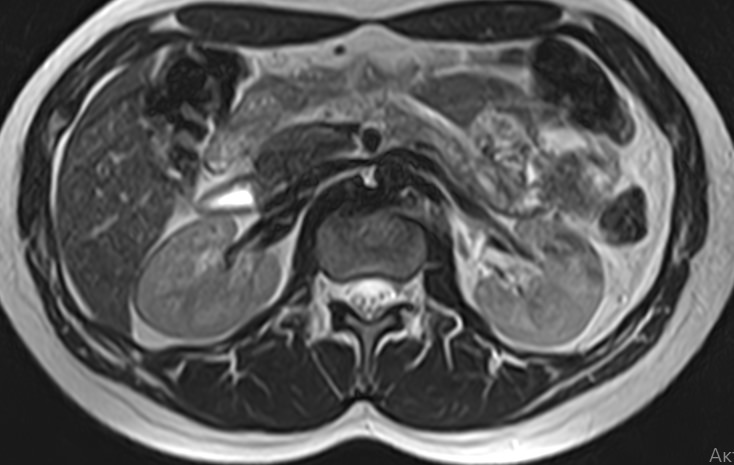

Мочеточники — это парные трубчатые органы, длиной приблизительно 25-30 см, соединяющие почечные лоханки с мочевым пузырем. Наиболее частой патологией является нарушение оттока мочи по мочеточнику за счет сужения (стриктуры) или обтурации (полной закупорки) его просвета.

Магнитно-резонансная томография позволяет получить информацию о состоянии мочеточников и окружающих мягких тканей для точной диагностики заболеваний данной анатомической области.

Что показывает МРТ мочеточников

В первую очередь необходимо отметить, что магнитно-резонансная томография мочеточников выполняется в комплексном обследовании почек и мочевыводящих путей, как самостоятельный метод диагностирования невозможен.

При помощи магнитно-резонансной томографии удается оценить состояние органов и выявить имеющиеся патологии: